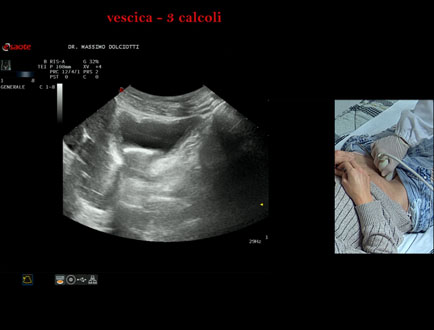

Sonda: Convex Multifrequenza 1-8 MHz

Età Paziente: F 45 anni

Motivazione dell'esame: da alcuni mesi, disuria ed infezioni urinarie recidivanti.

Commento all'esame: le immagini ed il video documentano 3 immagini iperecogene, con cono d'ombra posteriore, da ricondurre a litiasi multipla della vescica.

Conclusioni: 3 calcoli della vescica (3 bladder stones).